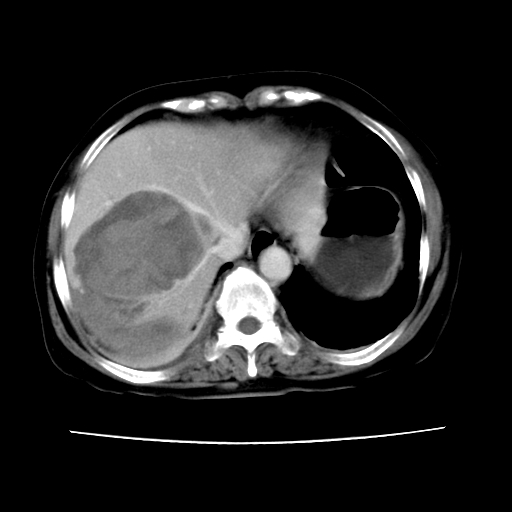

ct增强

考虑肝腺瘤出血可能,肝血管瘤增强表现不是很典型,放在第二。

考虑为肝血管瘤破裂出血并肝包膜下血肿;右侧少量胸腔积液。

6月份ct片显示肝内巨大混杂密度团块,伴包膜下积液(内含液液平面),增强多无明显强化。只能考虑肝占位病变,并肝内、血膜下血肿。肝ca并出血多见,而肝血管瘤并破裂出血少见。

从平扫+增强及治疗后复查片,病变明显缩小,不考虑肝癌出血可能,还是考虑为良性病变可能性大;单纯血肿并包膜下积液吧,病变强化没法解释,肝血管破裂出血吧,增强不符合典型血管瘤的表现,良性肿瘤破裂出血吧,复查片看来好像也不太支持(没做强化也不太好说)。本人还是考虑单纯肝内血肿并包膜下积液,强化是不是血管有外渗。